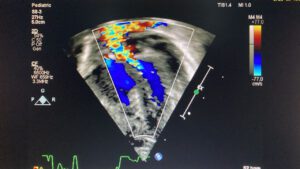

تمكّن بفضل الله أطباء مركز الأمير سلطان لطب وجراحة القلب بالقصيم “قسم أمراض القلب لدى الأطفال” من إجراء عملية ناجحة لإنقاذ حياة طفل حديث الولادة يزن ٣ كيلو، كان يعاني من انعكاس في الشريان الرئوي سبب له توقف في القلب بسبب نقص في نسبة تشبع الدم للأكسجين بنسبة (٣٥ ٪) حيث أُجريت له عملية جراحية لتركيب وصلة شريانية بدون إستخدام جهاز القلب والرئة الصناعية، وقد تكلّلت العملية ولله الحمد بالنجاح وتم نقل الطفل للرعاية القلبية لمتابعة حالته.